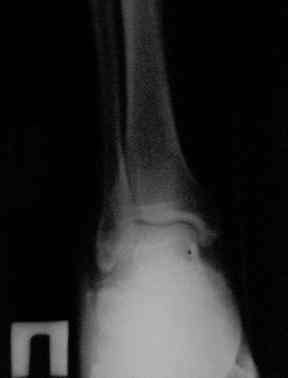

С левой стопой дело похуже. Нужен прямой снимок, да и боковой не помешает повторить на всю стопу, ну и плюс аксиальный. Готовтье аппарат.

Отправляю снимки(свежие)и фото стоп.

С уважениемД.Б.